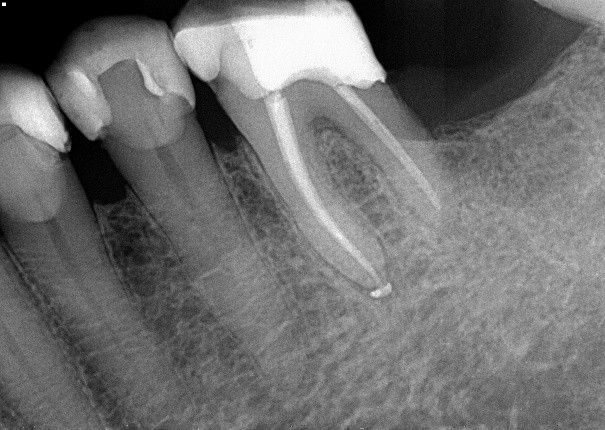

1. (Select ONE OR MORE correct answers)

The radiograph shows evidence of

2 / 50

2. (Select ONE OR MORE correct answers)